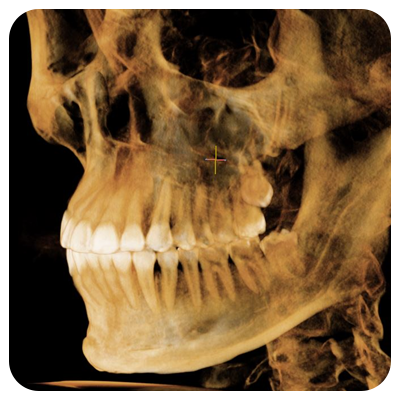

junio 5, 2019La cefalometría es una técnica de gran utilidad en odontología y especialmente en la ortodoncia, ya que permite obtener medidas del cráneo a partir de radiografías que luego se calcan sobre un acetato para establecer los puntos anatómicos más significativos y medir las distancias y relaciones entre unos y otros (huesos, músculos, dientes, etc.) atendiendo a diferentes criterios para luego compararlos con los patrones de normalidad.

Es por esta razón que la cefalometría es un procedimiento diagnóstico fundamental antes de iniciar cualquier tratamiento ortodóncico, ya que permite determinar las anomalías morfológicas, de colocación y de crecimiento de los dientes, para así establecer el objetivo del tratamiento y poder realizar el adecuado seguimiento del mismo.